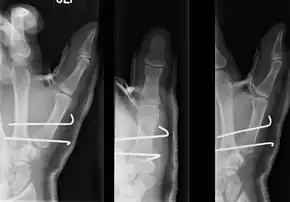

- For Bennett fractures where there is between 1 mm and 3 mm of displacement at the trapeziometacarpal joint, closed reduction and percutaneous pin fixation (CRPP) with Kirschner wires is often sufficient to ensure a satisfactory functional outcome. The wires are not employed to connect the two fracture fragments together, but rather to secure the first or second metacarpal to the trapezium.